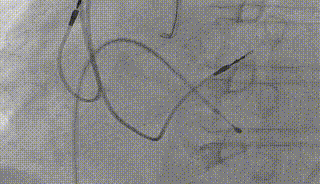

右冠保护

第一次释放

第二次释放

反复造影确认冠脉风险